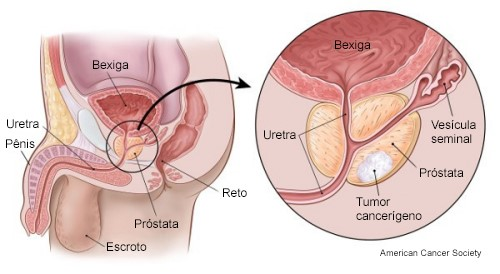

Em fases iniciais, o câncer de próstata raramente apresenta sintomas. Sintomas urinários, como jato fraco, são geralmente causados por crescimento benigno da próstata (hiperplasia prostática benigna – HPB). Quando há sintomas relacionados ao câncer de próstata, como retenção urinária, disfunção erétil, dilatação do rim ou dor óssea, o câncer já é localmente avançado ou metastático. A suspeita de câncer de próstata surge com exames de rotina, como o PSA (sangue) e o toque retal. A ressonância magnética pode guiar a necessidade de biópsia, que é o único exame que confirma o diagnóstico.

A maioria dos casos é detectada em estágio inicial e é curável. O câncer pode estar localizado ou ter se espalhado (doença metastática). O escore de Gleason e os graus ISUP classificam a agressividade do tumor. Exames como Cintilografia Óssea, Tomografia e, principalmente, PET-CT com PSMA, avaliam a extensão da doença.

Uma característica notável do câncer de próstata , mesmo em sua fase inicial e restrito à glândula, é sua natureza multifocal. Isso significa que múltiplos focos tumorais podem coexistir dentro da mesma próstata, o que representa um desafio significativo para a eficácia de terapias focais, como o HIFU (Ultrassom Focalizado de Alta Intensidade), ou ressecções parciais. Por essa razão, os tratamentos locais mais estabelecidos e eficientes para curar o câncer de próstata localizado geralmente envolvem a abordagem de toda a glândula. Para os casos de câncer de próstata avançado ou metastático, são necessárias combinações de tratamentos sistêmicos, os quais se mostram muito eficazes no controle da doença e na melhoria da qualidade de vida do paciente.